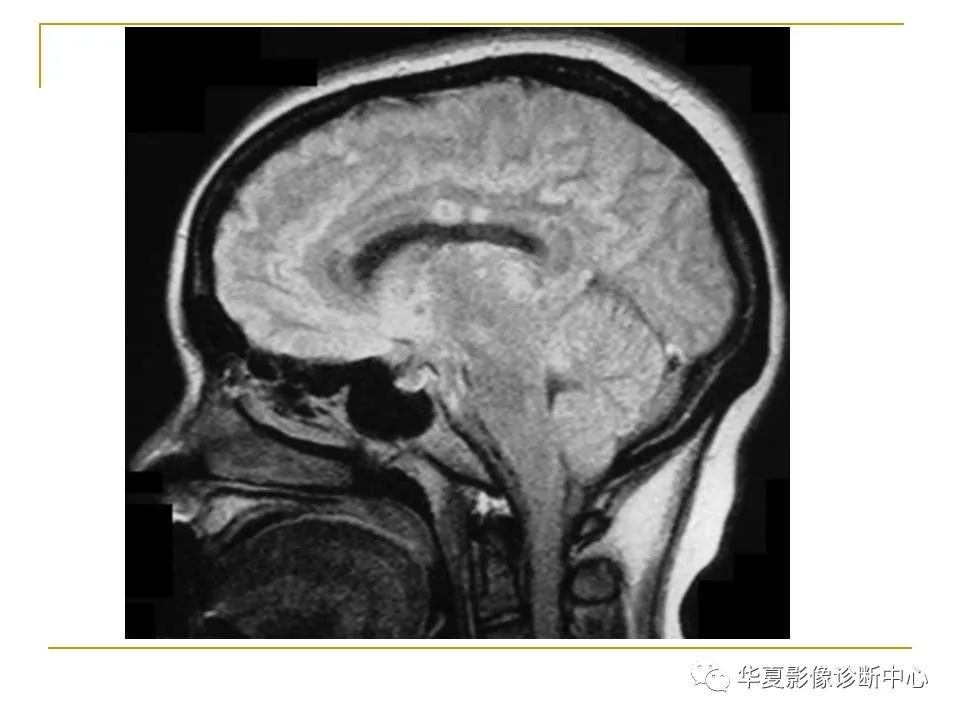

胼胝体解剖及病变大全